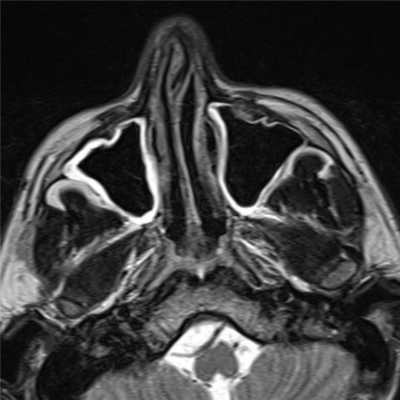

(Слева) На корональной КТ в костном окне определяется ПФД с поражением глазницы, петушиного гребня, решетчатого лабиринта, средней носовой раковины справа. Оцените типичную картину «матового стекла». Носовая перегородка смещена влево.

(Справа) На аксиальной МРТ (Т2ВИ) у этого же пациента определяется выраженный гипоинтенсивный сигнал в пораженных костях. Поражение однородное и сопоставимо с «матовым стеклом» на КТ. При большем количестве фиброзной ткани ожидаемы очаги с более интенсивным сигналом и более длительным временем повторения.